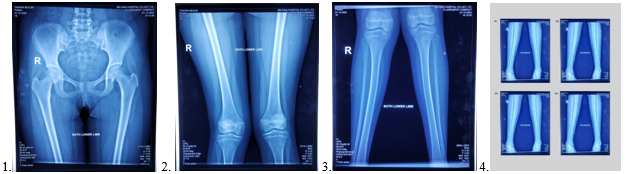

1, 2 & 3 Pre-operative x-ray of pelvis & both lower limbs. 4. CORA analysis.

5 & 6 Post-operative x-ray 7 & 8 Follow up x-ray.

A 15 years old adolescent girl came with the complaints of abnormal walking due to right knee bending inwards, also during standing position. She was perceived pain in right knee during walking and longtime standing position. She has H/O- fractured proximal tibia (Rt.) more than 6 months ago due to trauma and treated conservatively by long leg full plaster. Plaster removed after 3 months. One month later she developed pain in knee joint during walking and right knee gradually bend inwards. After more than 6 months of her primary fracture, when the problems worsening she was came to us with above complaints. O/E- Bil genu valgus right > left. Clinically, right knee -300 and left knee -100 valgus. There was 1.5 cm shortening of right lower limb than left. Previous fractured x-ray was not found. Both right and left lower limb with pelvis full radiograph was done. In x-ray both femurs and knee joints were normal. In radiograph, the medial and lateral surfaces of right tibia with fibula bend medially. Left tibial surfaces and fibula appears almost normal. The right tibia at the point of 14 cm from upper end there was maximum angulation point. The degree of genu valgus was evaluated by CORA method and treatment plan set accordingly. There was 300 medial bending of right tibial shaft and about 100 of left tibial shaft. The patient was diagnosed as post traumatic unilateral right tibial genu valgus following proximal tibia fracture.

Lower limbs deformity can be evaluated by long film x-ray of both lower limbs with pelvis A/P view, Q angle (Quadriceps angle), tibio-femoral angle and CORA (Center of Rotation of Angulation) method. 6,7,17

CORA (center of rotation of angulation)

In deformed tibia, CORA determination is so simple, because both mechanical and anatomical axes are amalgamate and goes through center of tibial diaphysis. The anatomical axis of each segment of deformed tibia drawn on x-ray, the lines will intersect and the acute angle between the lines is CORA.